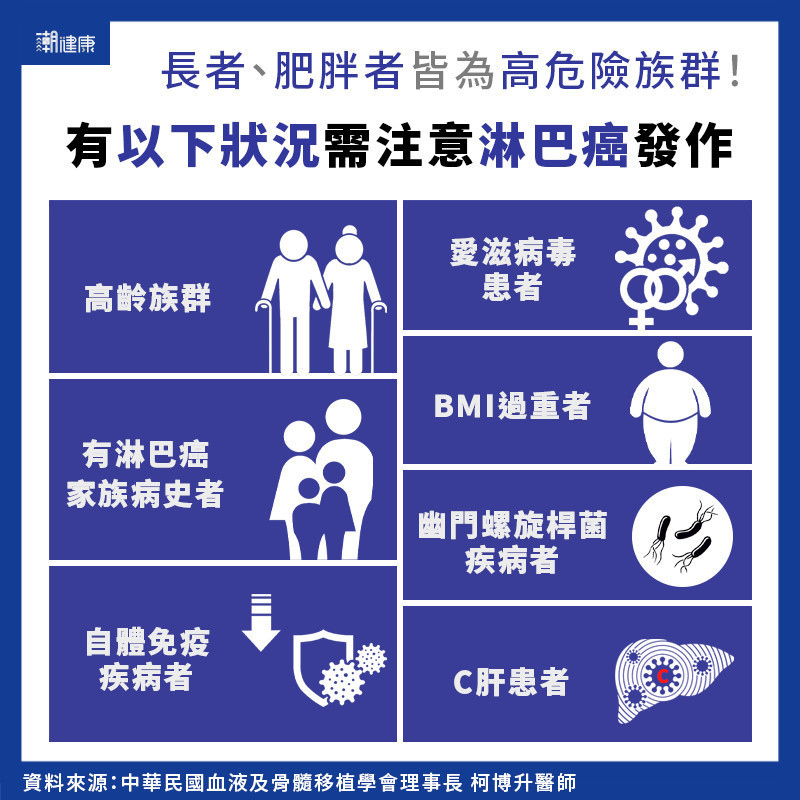

發燒2個月確診! 醫揭淋巴癌6症狀:盜汗疲累、淋巴腫莫輕忽 | 潮健康 COOL HEALTH | 集結最新健康、潮流、知識的新媒體平台

發燒2個月確診! 醫揭淋巴癌6症狀:盜汗疲累、淋巴腫莫輕忽 | 潮健康 COOL HEALTH | 集結最新健康、潮流、知識的新媒體平台